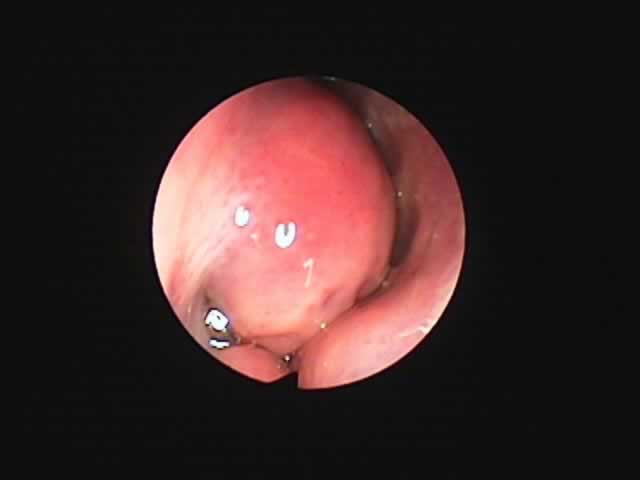

扁桃のコブレーション手術(日帰り手術)

| 左扁桃術直後(31歳男性,6月9日) 数カ所針電極を刺入 | 白い部分が変性部位(6月11日) | 右扁桃術直後(7月7日) |